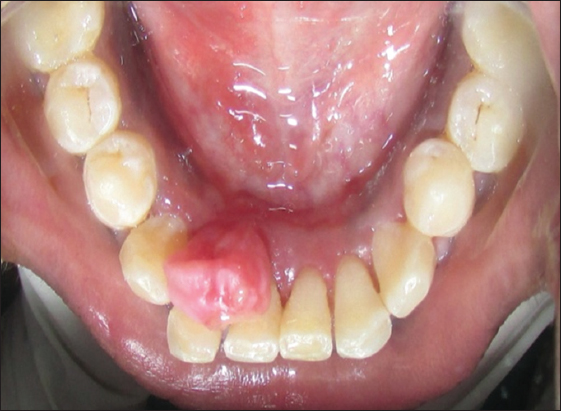

A 22-year-old female patient was reported to the outpatient department with a chief complaint of a growth in the lower front teeth region since 5–6 months earlier with no relevant medical history. The lesion was gradually increased in size from the interdental papilla of lower left lateral incisor with a history of difficulty in mastication and speech. Intraoral clinical examination revealed a pedunculated firm in consistency and well-defined growth in relation to 31, 32, and 33 on the lingual side measuring approximately 1 cm × 1 cm in diameter, extending from distal surface of 31 to mesial surface of 33, upper border covers the middle third level of 31, 32, and 33 pink in color, roughly oval, with overlying smooth surface, and surrounding mucosa is normal and borders are well defined [Figure 1]. On palpation, the growth is non-tender, firm in consistency, mobile, and having pedunculated base. Labial vestibule was apparently normal with respect to 31, 32, and 33 hard tissue examination revealed normal.

Figure 1: Pre-operative